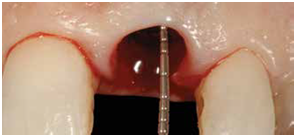

98/01/08經過三個半月做右下第一小臼齒的二階暴露,發覺鄰牙的植體高度竟已掉下來

980305幫患者補角化牙齦並翻開清除發炎組織,期待能阻止繼續骨破壞